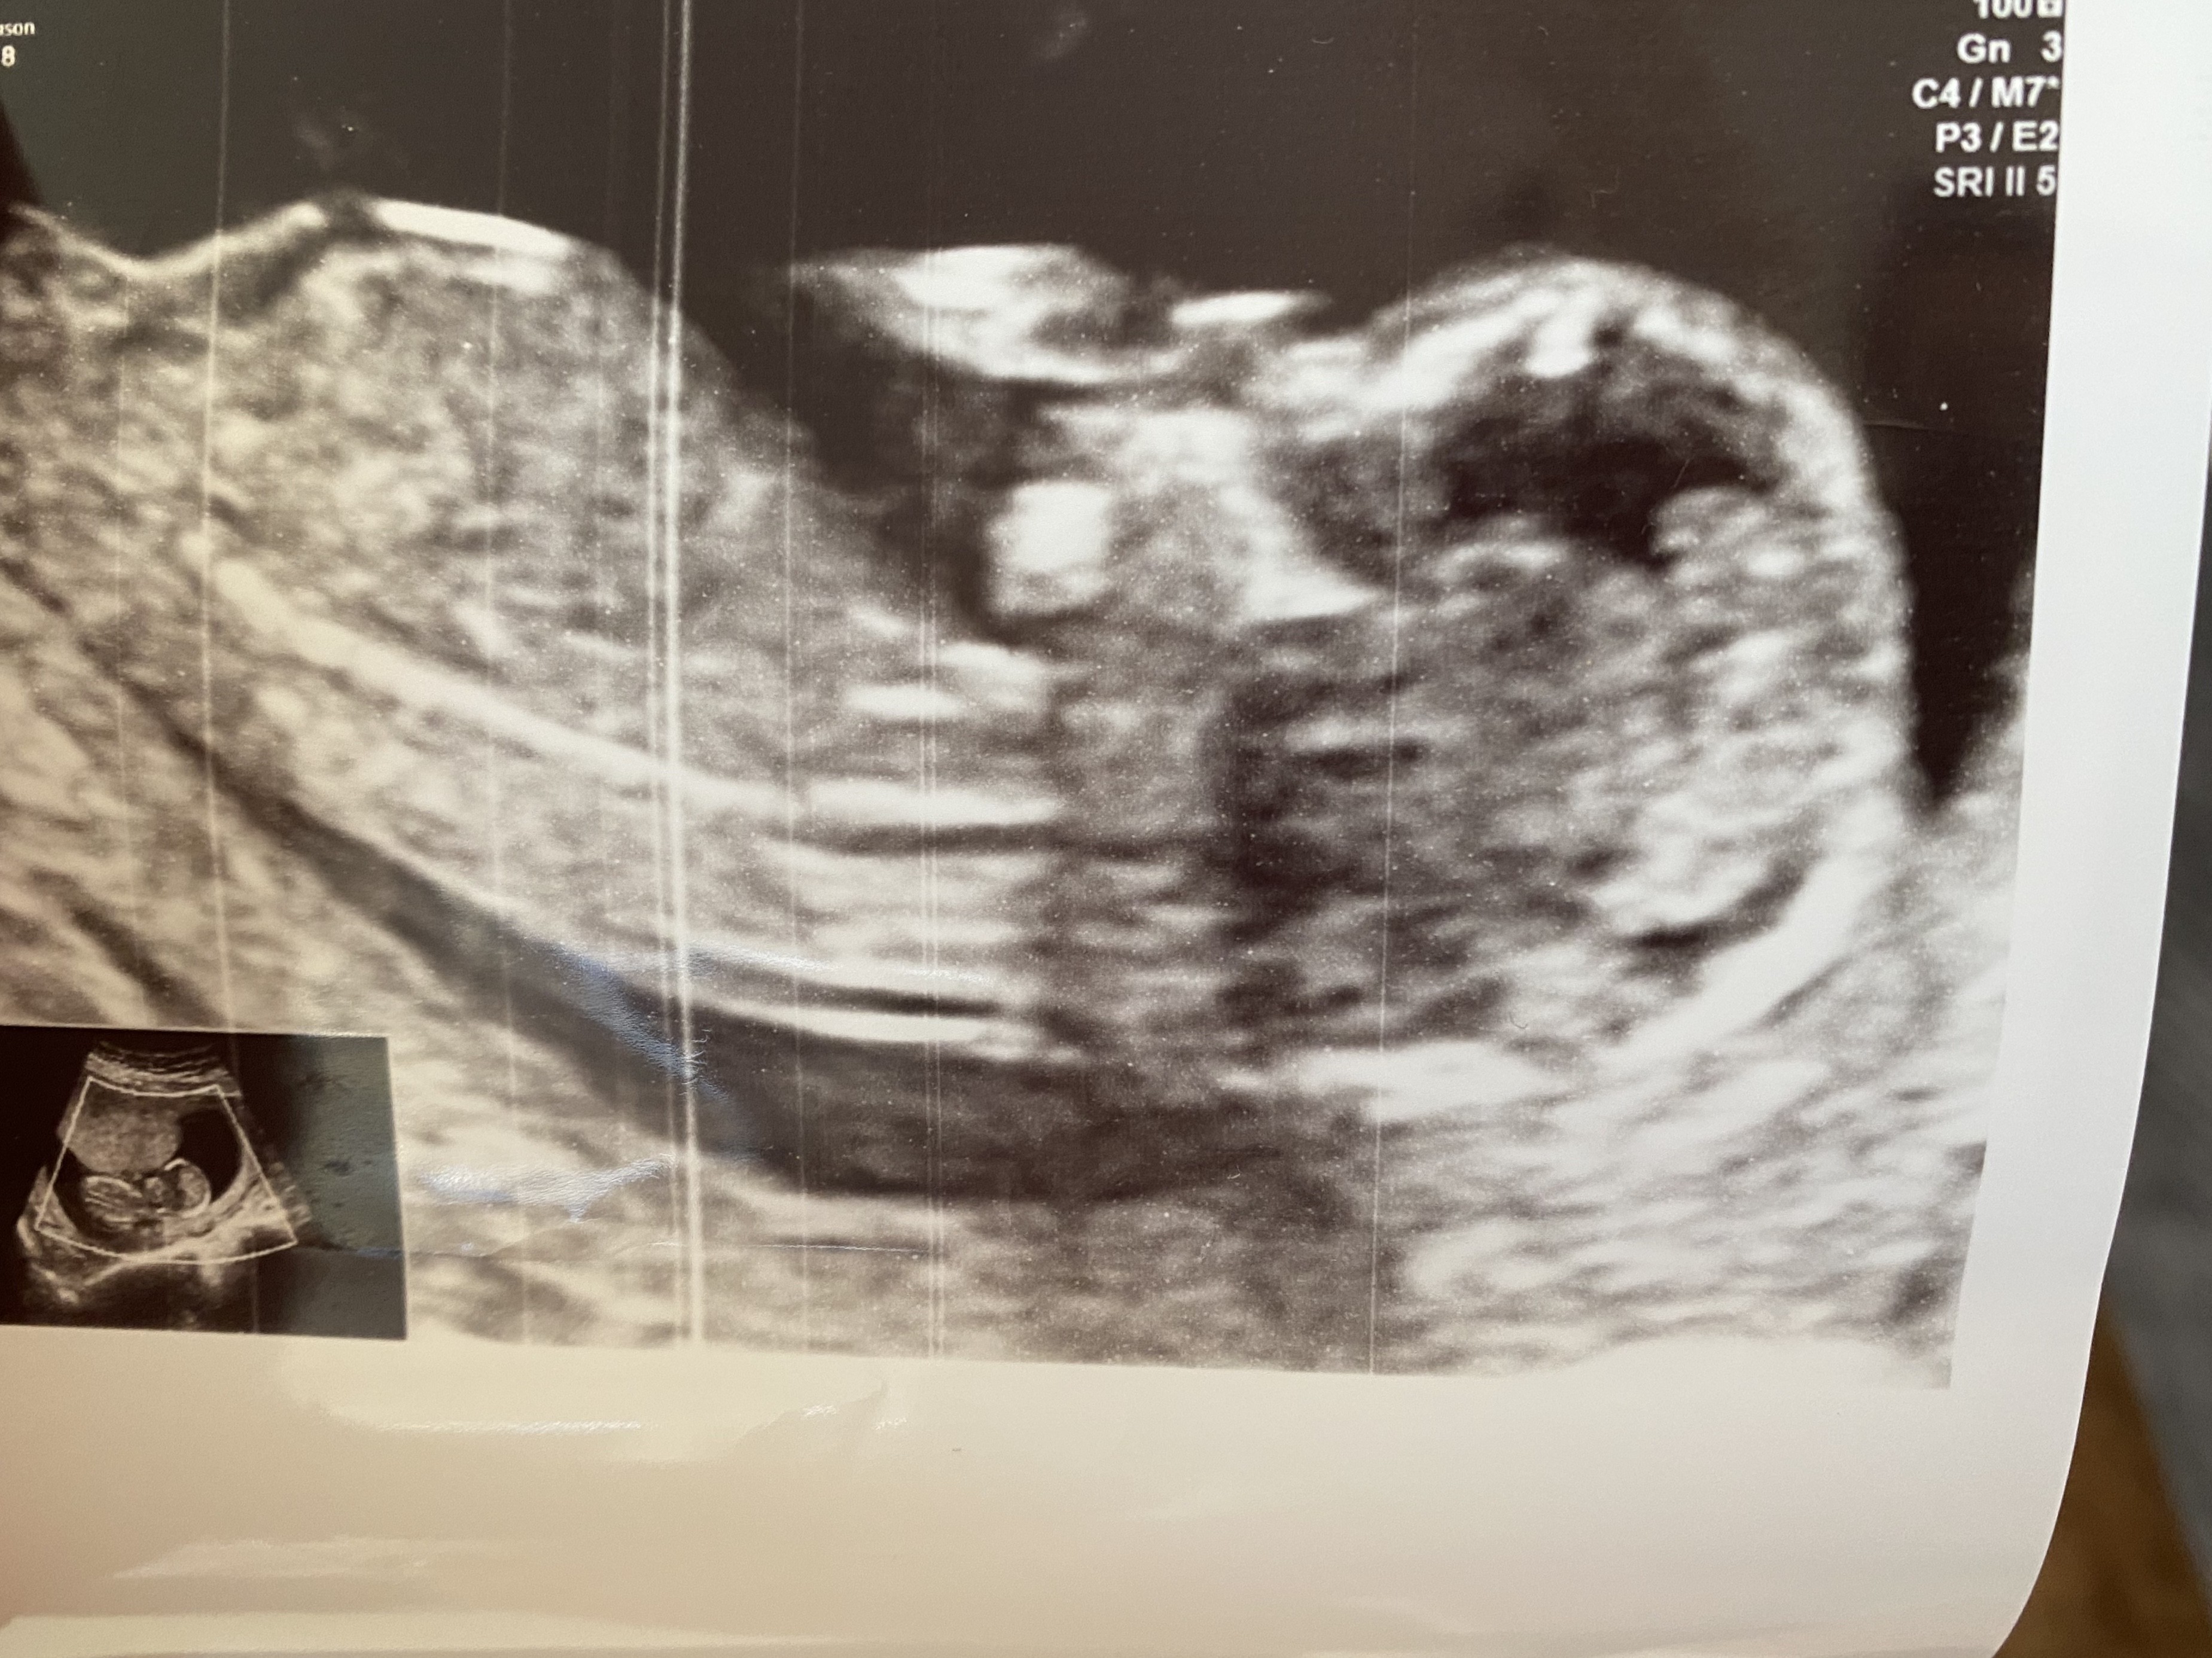

Hej. Na usg prenatalnym w 13 tyg ginekolog powiedziala mi, ze najprawdopodobniej chłopiec (wywnioskowala po tym między nogami). Wstawiłam na grupę fb zdjecie usg i pisali, ze z NUB wychodzi dziewczynka :/ Czy u Was tez ta metoda sie sprawdziła? Ciezko mi w to teraz uwierzyć bo ginekolog mowila, ze z boku nie widac dokladnie tego wyrostka bo pytałam ją o metodę nub. Jaka to ma skuteczność?

Teoria nub ma wysoką skuteczność. Natomiast odczytywanie jej przez niedoświadczone osoby jest obarczone dużym ryzykiem błędu. Po pierwsze trzeba dobrego ustawienia się dziecka, a po drugie sprawnego, lekarskiego oka.

Moim zdaniem musisz uzbroić się w cierpliwość. A ocenę wyrostka przez osoby z fb traktuj bardziej jako ciekawostkę niż jako pewnik 😊

U mnie się żadne teorie nie sprawdziły. Z teorii Ramziego wychodził chlopiec, z NUB w 12 tygodniu na usg genetycznym lekarz stwierdził, że chłopiec. W 18 tygodniu zmieniło się na dziewczynkę i tak już zostało. Urodziłam córkę. Dlatego moim zdaniem, żeby mieć pewność to lepiej poczekać trochę, a nie gdybać na wczesnym etapie ciąży. Jednak mimo wszystko bardziej wierzyłabym lekarzowi niż grupie na Facebooku.